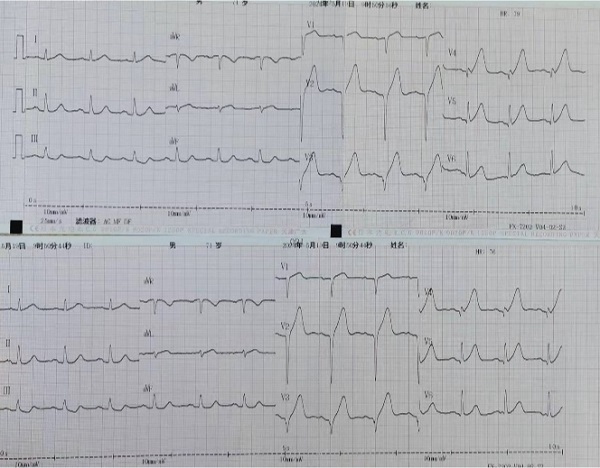

陕西健康集团二一五医院国家级胸痛中心迅速启动应急预案,随着绿色通道迅速打开,王先生的“生命倒计时”终于按下了暂停。在医院的走廊里,时间仿佛变得缓慢而沉重,胸痛中心医护人员化身“守护神”,迅速而有序地进行各项检查和治疗。刘积伦主任团队也凭借着丰富的临床经验,迅速且准确地判断出了病因——急性心肌梗死。

时间紧迫,容不得丝毫犹豫,刘积伦主任团队在告知患者家属相关病情后,立即为患者进行了紧急冠脉造影及支架植入术。手术中,医护人员每一个动作都精准而果断,很快,闭塞的血管被成功开通,恢复3级血流,王先生的心脏重新焕发了生机。